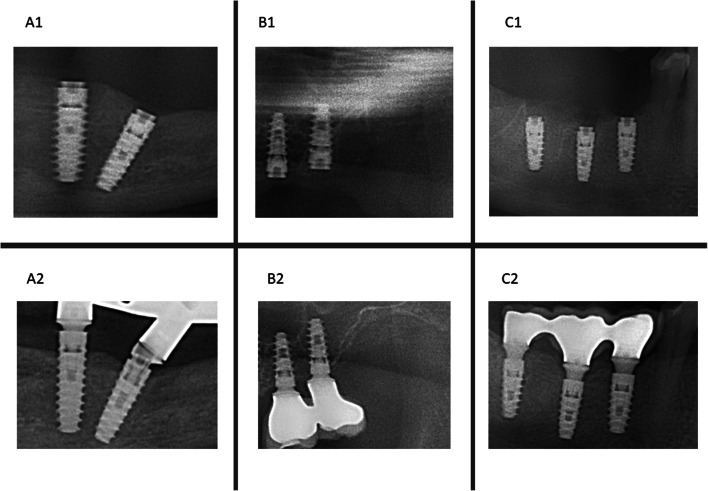

Purpose: The aim of this study was to evaluate the marginal bone loss (MBL) over a follow-up period of up to 36 months in Immediate dental implants (IDIs), as well as the impact of various clinical variables on the MBL.

Methods: IDIs placed in two surgical phases were evaluated. Implants were classified into bone loss (BL, exposed threads), bone remodeling (BR, crestal bone at the implant margin ± 0.1 mm), and bone overlapping (BO, bone above the abutment).

Results: A total of 1,040 IDIs were inserted in 344 patients with a successful osseointegration rate of 98.9%. The average MBL at 2, 6, 12, 24, and 36 months was - 0.3 ± - 1.0 mm, - 1.1 ± -1.8 mm, - 1.4 ± - 1.8 mm, - 1.7 ± - 1.9 mm, and - 1.3 ± - 2.3 mm, respectively. In the Baseline-12-month period, 17.5% of the IDIs presented BL, 9% BR, and 73.5% BO. For the B1-12 month period, 19.8% presented BL, 10.7% BR, and 69.5% BO. Mixed regression models showed significant MBL overtime pre-loading (p < 0.0001), stabilizing at 8.5 months from implantation. Immediate mandibular implants had lower MBL (p = 0.0365). Post-loading, MBL was lower in the mandible (p = 0.0095) and positively influenced by abutment height and rotational abutments.

Conclusions: The present study supports the clinical efficacy of the IDIs placement protocol with high survival rates and acceptable MBL. It is recommended to place bone level implants slightly below the crest to ensure the platform remains at an optimal depth during the initial bone remodeling phase post-implantation.